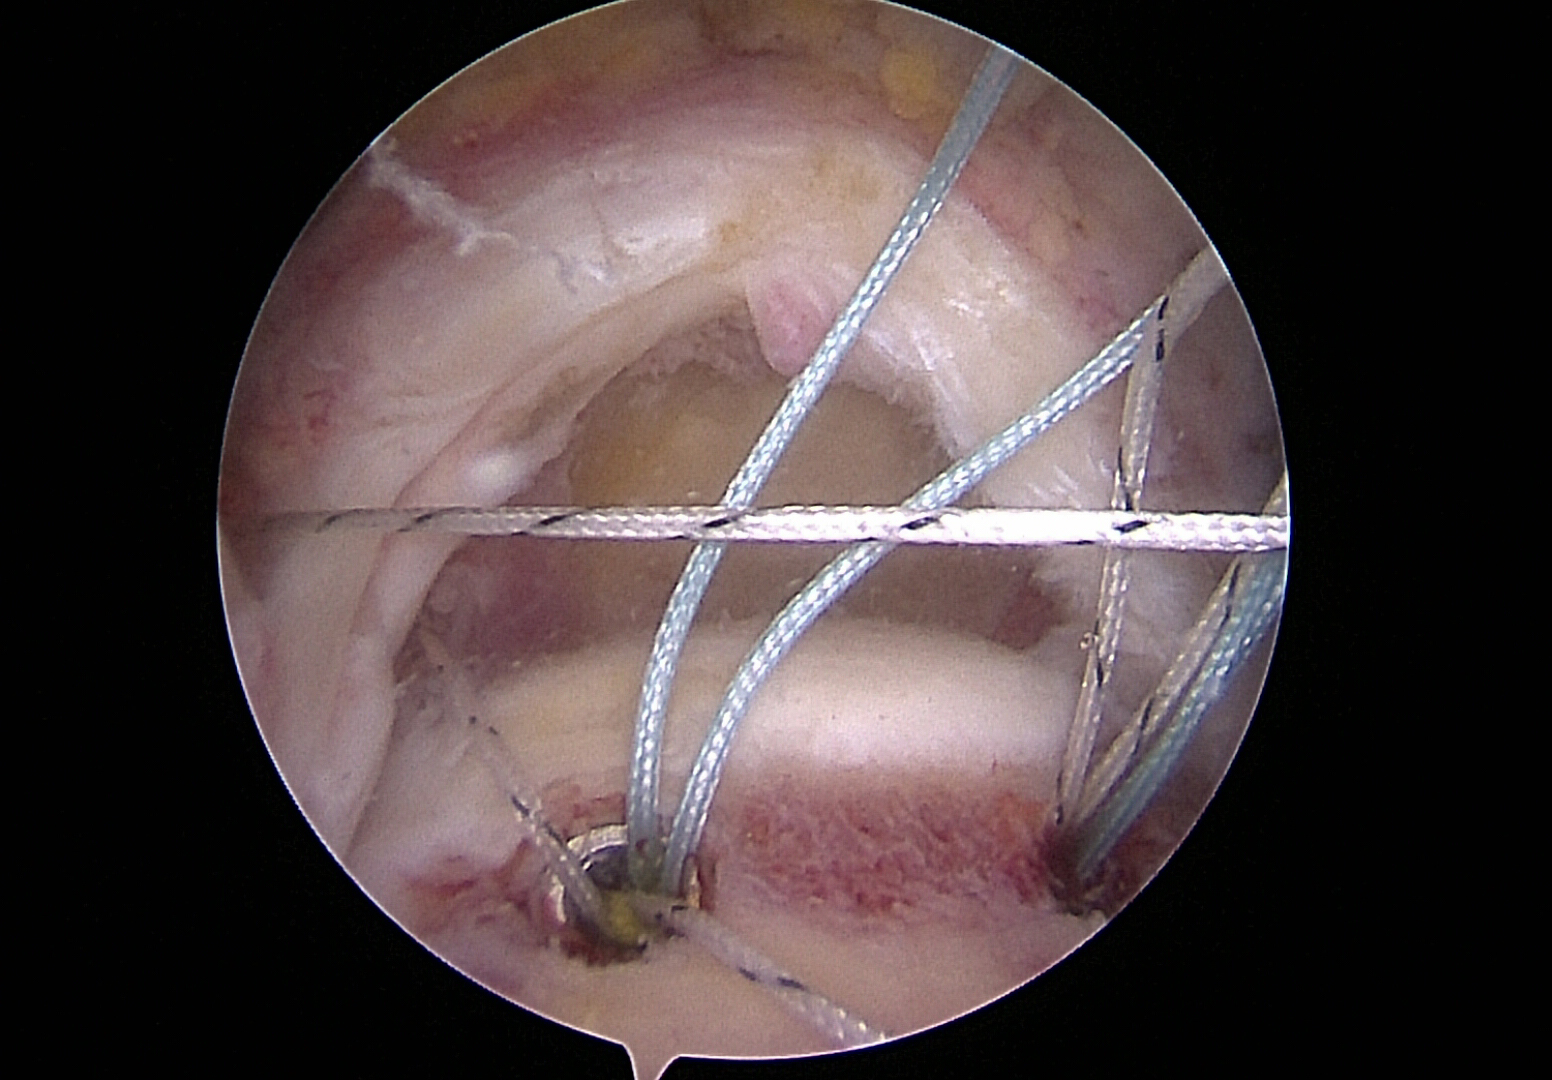

Anchor sutures placed for reconstruction of the rotator cuff

Anchor threads presented through tendon for reconstruction